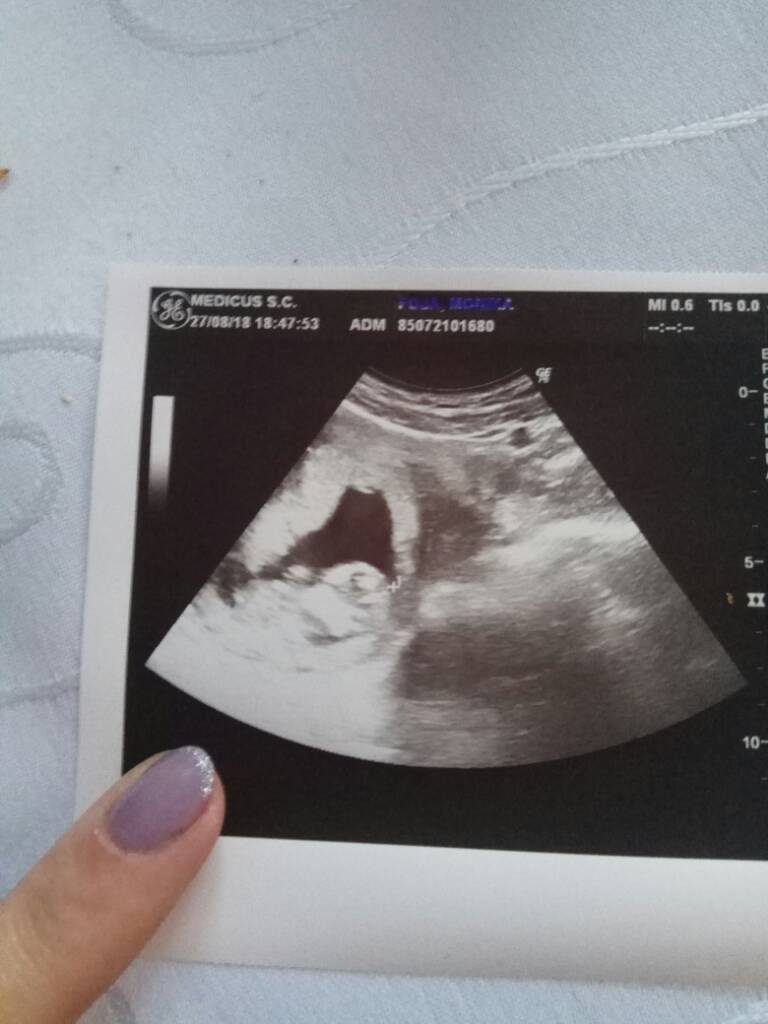

PięknieOj dziewczyny chyba mocno kciuki trzymałyście maleństwo zdrowe rośnie ma już 5.05cm I pięknie bijące serduszko Zobacz załącznik 892312

Cudnie [emoji173]Oj dziewczyny chyba mocno kciuki trzymałyście maleństwo zdrowe rośnie ma już 5.05cm I pięknie bijące serduszko Zobacz załącznik 892312

I niech zdrowo rośnie [emoji6]Oj dziewczyny chyba mocno kciuki trzymałyście maleństwo zdrowe rośnie ma już 5.05cm I pięknie bijące serduszko Zobacz załącznik 892312

Super !! [emoji171] [emoji171]Oj dziewczyny chyba mocno kciuki trzymałyście maleństwo zdrowe rośnie ma już 5.05cm I pięknie bijące serduszko Zobacz załącznik 892312